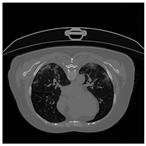

To address contrast-related issues, such as noise and grayscale inhomogeneity commonly observed in CT-scans, the Contrast Limited Adaptive Histogram Equalization (CLAHE) [] method is implemented following the data-scaling step. CLAHE is specifically utilized to alleviate these problems and enhance the visualization of CT-scans. By applying the CLAHE method, image noise is effectively reduced, while simultaneously generating pixels with improved grayscale contrast []. Consequently, CT-scans become more visually discernible, aiding in the accurate analysis and interpretation of the images. A comparative illustration of CT-scan samples before and after the application of the CLAHE method is presented in Table 4 [], highlighting the significant enhancement achieved through this preprocessing technique.

Table 4.

CT-scan comparison before and after CLAHE application [].